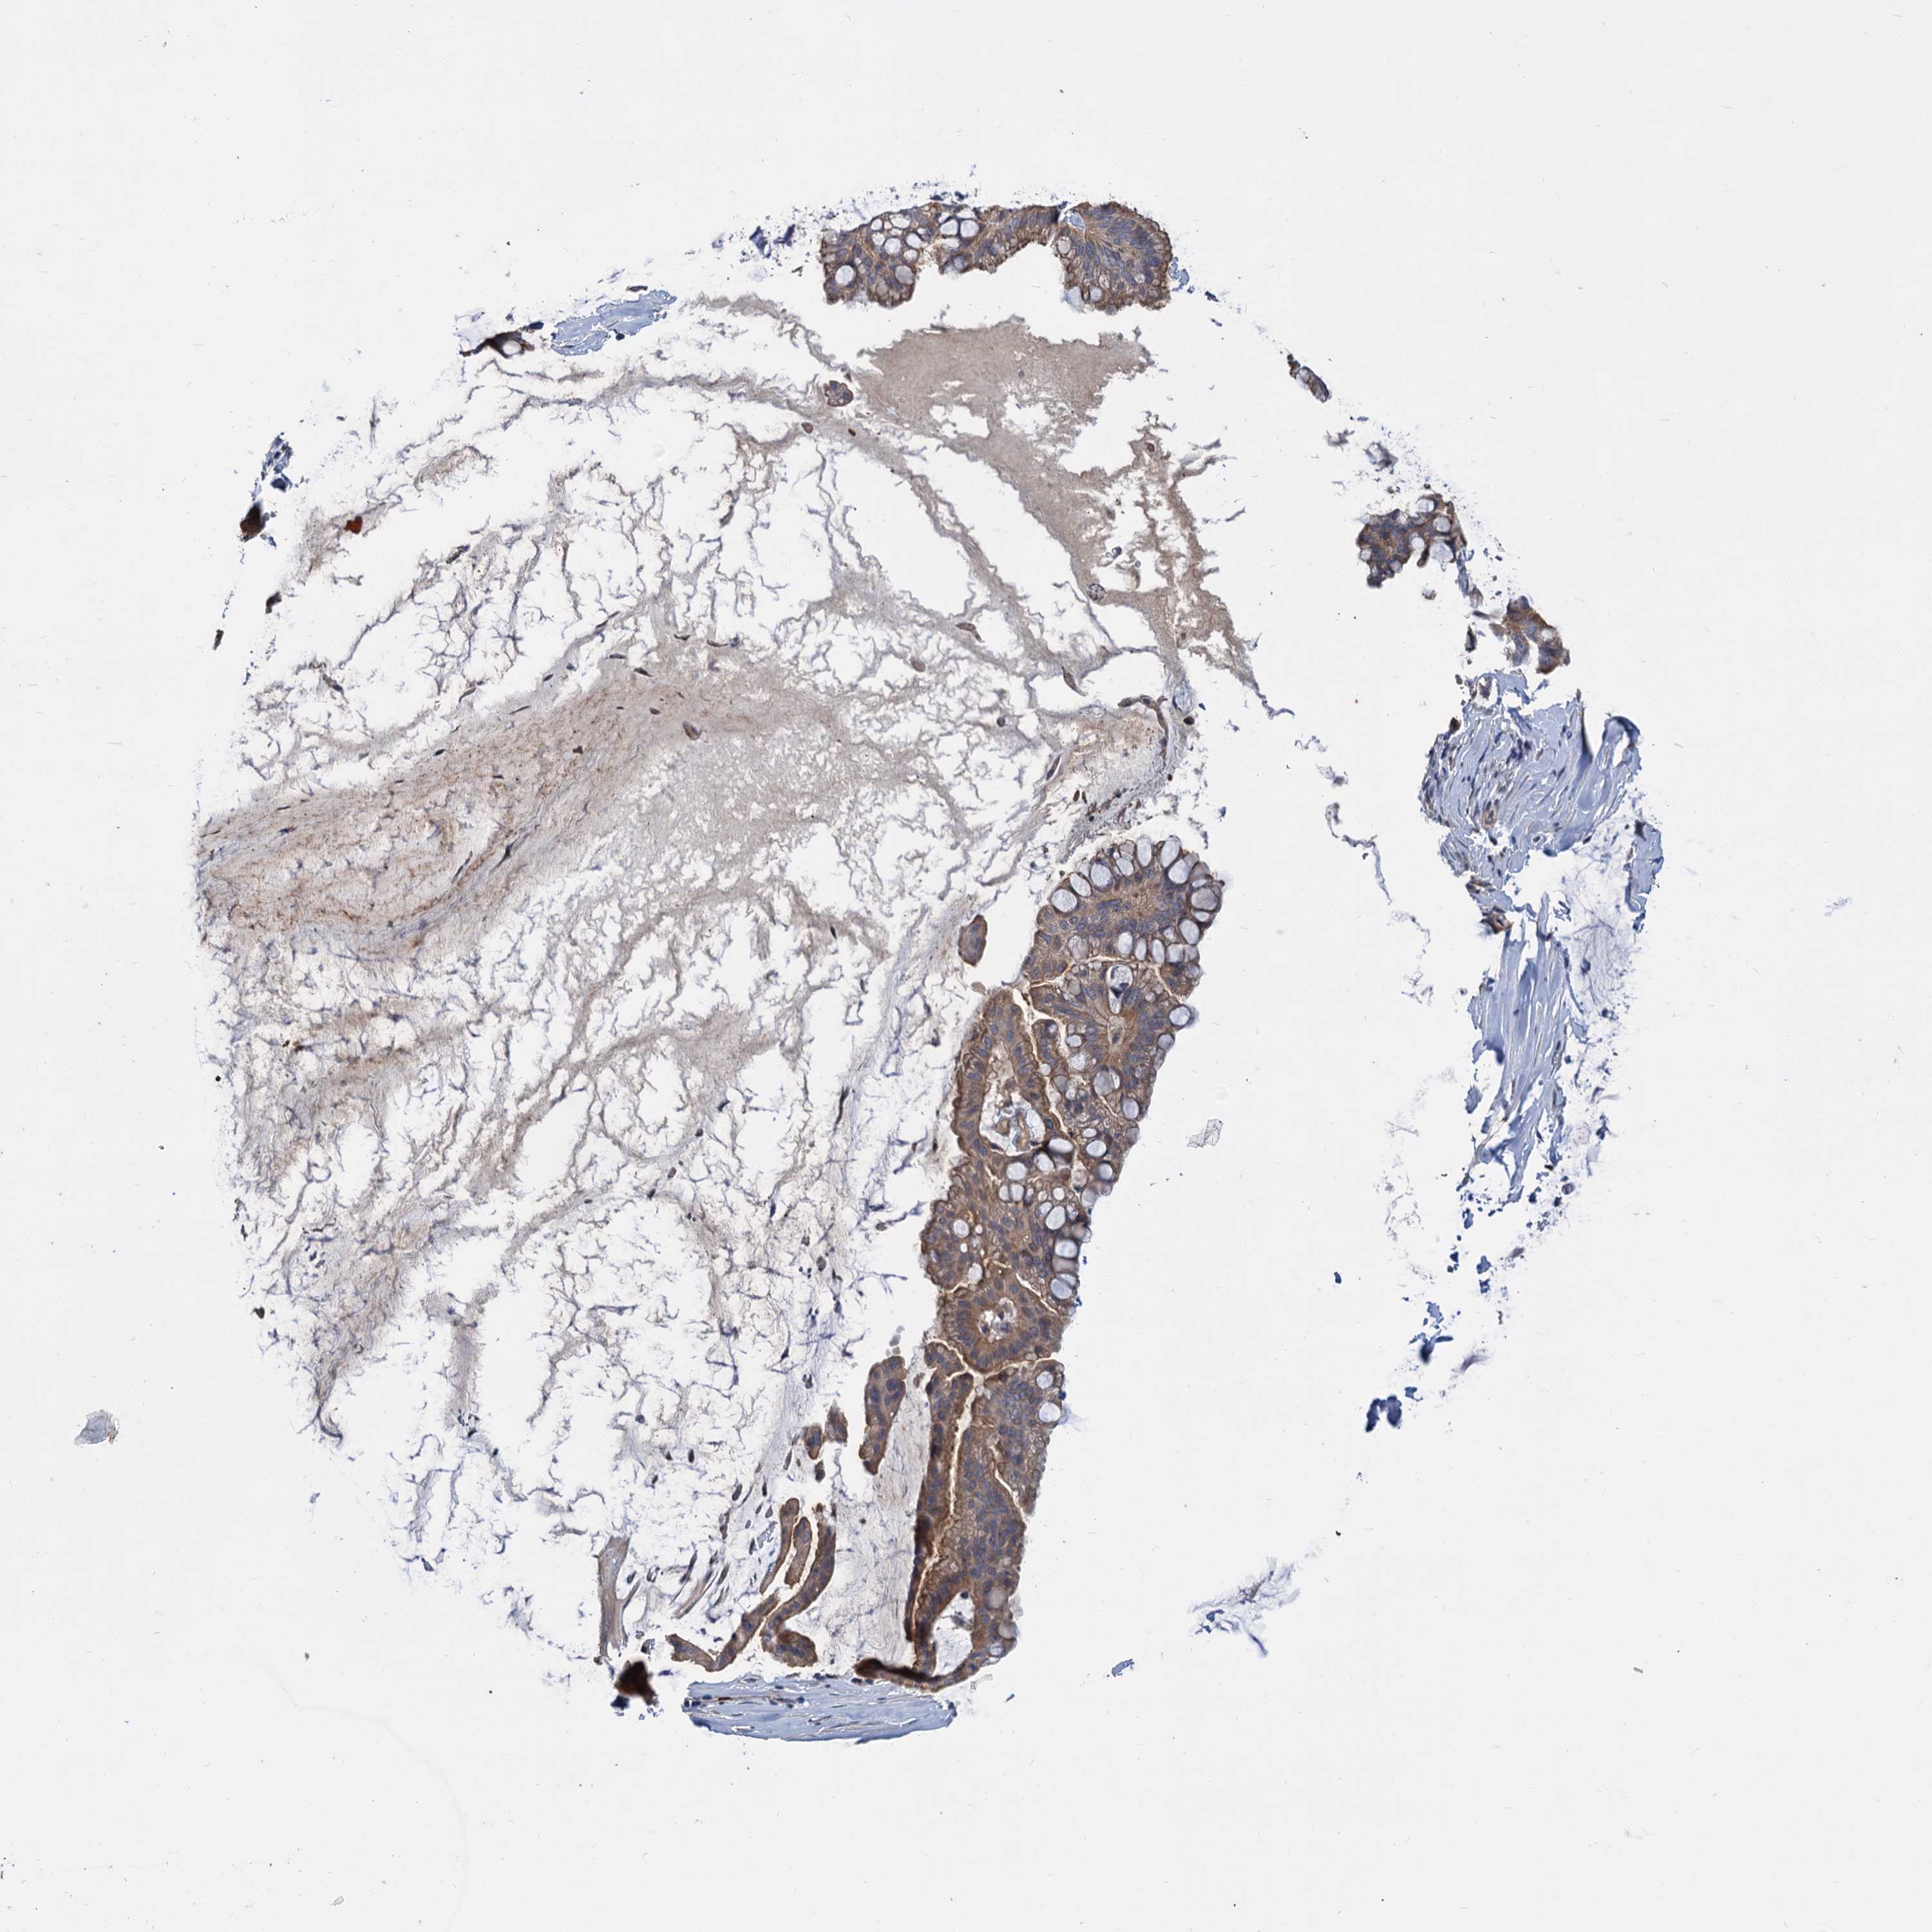

OVARIAN CANCER - Protein expressioni

A mouse-over function shows sample information and annotation data. Click on an image to view it in a full screen mode. Samples can be filtered based on level of antibody staining by selecting one or several of the following categories: high, medium, low and not detected. The assay and annotation is described here.

Note that samples used for immunohistochemistry by the Human Protein Atlas do not correspond to samples in the TCGA dataset.

Antibody stainingi

Antibody staining in the annotated cell types in the current human tissue is reported as not detected, low, medium, or high, based on conventional immunohistochemistry profiling in selected tissues. This score is based on the combination of the staining intensity and fraction of stained cells.

Each image is clickable and will lead to virtual microscopy that enables deeper exploration of all samples and also displays staining intensity scores, fraction scores and subcellular localization as well as patient and tissue information for each sample.

Antibody HPA039015

Antibody HPA039016

Cystadenocarcinoma, serous, NOS

Carcinoma, endometroid

Cystadenocarcinoma, mucinous, NOS

Carcinoma, NOS